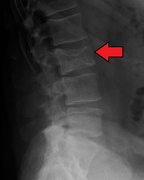

يُشخص المرض مخبريا بعمل عدة فحوصات و تشمل الفحوصات الوظيفية للكلية و قياس كمية الكالسيوم في الدم و عد مكونات الدم. و يستخدم الترحيل الكهربائي للبروتينات للتحري عن بعض البروتينات الغير طبيعية التي يتم إنتاجها بواسطة الخلايا السرطانية. للتحري عن أية كسور في العظام يتم تصوير المريض إشعاعيا بواسطة الجهاز الطبقي أو جهاز الرنين المغناطيسي.

X-ray of the forearm, with lytic lesions.

CT scan of the lower vertebral column in a man with multiple myeloma, showing multiple osteoblastic lesions. These are more radiodense (brighter in this image) than the surrounding cancellous bone, in contrast to osteolytic lesions which are less radiodense.